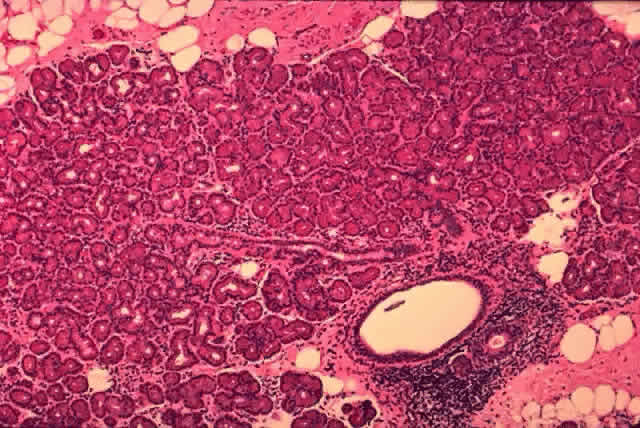

Each lobe of the lacrimal gland is separated into numerous lobules by interlobular fibrovascular connective tissue (Fig. 11). Each lobule, as seen by light microscopy, is composed of two units (Fig. 12): (1) the acinar unit (or secretory unit); and (2) the ductal system. The acinar units are further separated by intralobular fibrovascular connective tissue.

Fig. 11. Lacrimal gland architecture. Each lobe of the lacrimal gland is separated into numerous lobules by interlobular fibrovascular connective tissue. (H & E, original magnification × 5; Courtesy of Ralph Eagle, MD, Philadelphia, PA)

Fig. 12. Lacrimal gland. Each lobule is composed of acinar secretory units (above) and a ductal system. An interlobular duct is seen (lower right). (H & E, original magnification × 25; Courtesy of Ralph Eagle, MD, Philadelphia, PA)